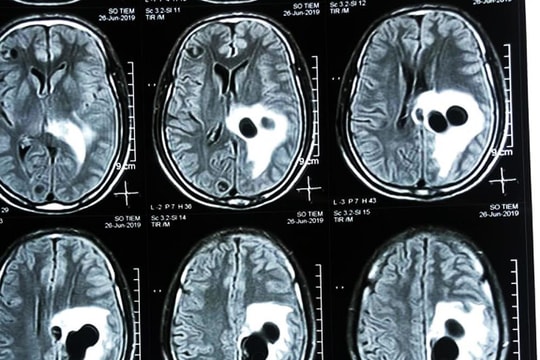

患者食用生血布丁后,脑部出现了绦虫寄生。

(Baonghean.vn)——患者罗文S(38岁,居住于归合县)长期遭受头痛和偏瘫的困扰。入院后,义安省的医生发现他脑内有寄生虫。